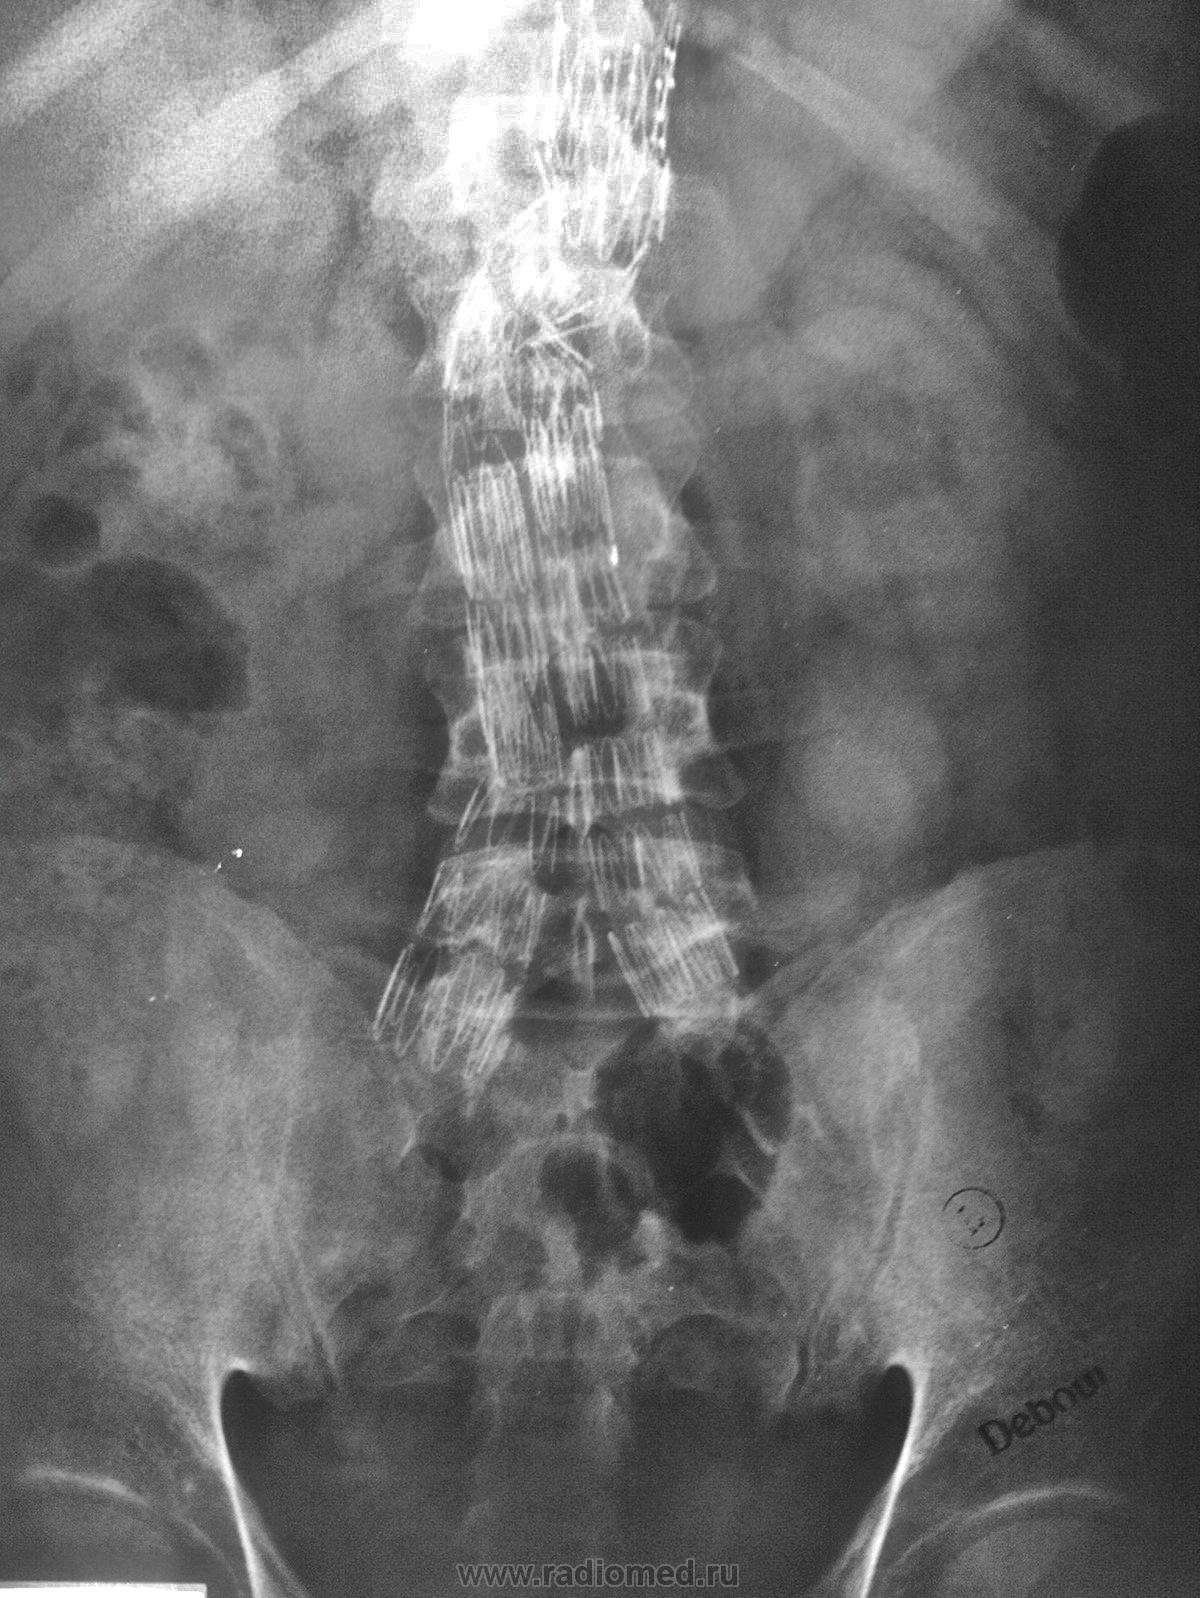

Нормы обзорной рентгенографии брюшной полости